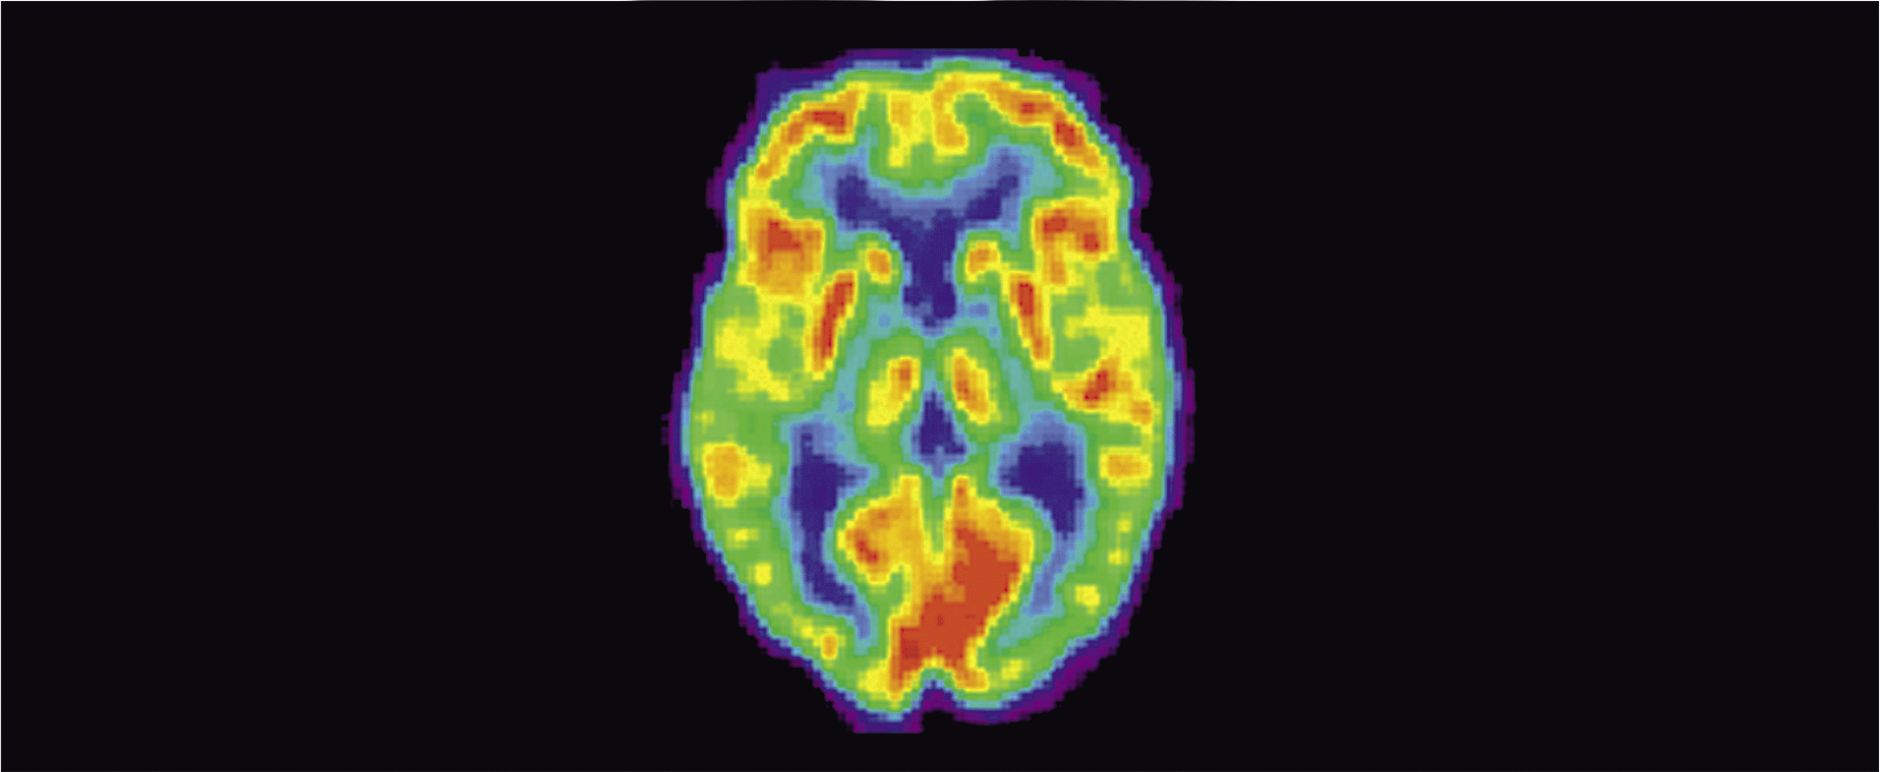

Позитронно-эмиссионная томография позволяет оценивать функциональные изменения на уровне клеточного метаболизма еще на ранних, «доклинических» стадиях заболевания, когда структурные методы нейровизуализации не обнаруживают каких-либо патологических отклонений [4] (рис. 5). Применение этого метода позволяет решать достаточно разнообразные задачи в неврологической практике, в частности прогнозировать течение болезни, в том числе оценить возможность восстановления поврежденной ткани после нарушения мозгового кровообращения, и анализировать эффективность проводимой терапии [19]. Однако ПЭТ также имеет ряд ограничений при ее использовании, препятствующих широкому применению метода в клинической и научно-исследовательской практике [4]. Многие из рассматриваемых вариантов МР-сканирования, как и ПЭТ, не входят в число стандартных или рутинных диагностических методов и используются преимущественно в научно-исследовательских целях. Это касается также воксельной МРТ-морфометрии – одного из наиболее распространенных вариантов МРТ-морфометрии, позволяющей вычислять объем серого и белого вещества головного мозга как в целом, так и в отдельности; выявлять фокальные очаги ишемии и изучать функциональное значение происходящих с течением времени изменений, например, более точно оценивать влияние церебральных ишемических очагов на степень утраты тех или иных функций у больных после инсульта [1].

Рис. 5. Позитронно-эмиссионная томография головного мозга